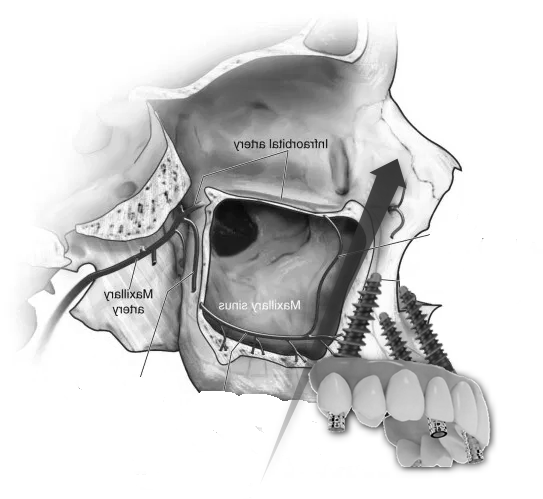

- Sinus Lift (Maxillary Sinus Elevation):

- At our center, we avoid this procedure thanks to Galileus Cerclage Sinus® surgery. In cases where the bone in the upper jaw is insufficient, a sinus lift procedure can be performed. This involves lifting the sinus membrane and adding bone graft material beneath it to improve bone density in the posterior maxilla.

- Zygomatic Implants:

- At our center, we avoid this procedure thanks to Galileus Cerclage Sinus® surgery. If not possible, we also avoid it with the Pterygoid Zygomatic technique. Zygomatic implants are longer implants anchored to the zygomatic bone (cheekbone). They are used when the maxillary bone is severely atrophied, providing an alternative to bone grafts or sinus lift procedures.